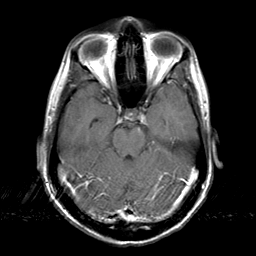

Sarcoma, MR Study #1 mr-gad -- Slice #7

[Home][Help][Clinical] Slice 7